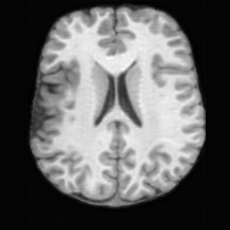

Healthy w/Lesion MaskPathologicalDifferencew/o LCGw/ LCG(a)Refer to captionRefer to captionRefer to captionRefer to captionRefer to captionRefer to captionHealthy w/Lesion MaskPathologicalDifferencew/o LCGw/ LCG(b)Refer to captionRefer to captionRefer to captionRefer to captionRefer to captionRefer to caption

Figure 7: Ablation study of Lesion Consistency Guidance (LCG). Without LCG, the generated pathological regions are indistinct and show weak pathological expression in both examples.

Lesion Consistency Guidance. Fig. 7 illustrates the impact of Lesion Consistency Guidance (LCG) for healthy-to-pathology editing. Without LCG, the generated lesion regions appear blurry around lesion boundaries, and the pathological patterns are less distinct, resulting in ambiguous lesion localization and weak pathological expression. Incorporating LCG produces lesions with more precise localization and well-defined shapes that better align with the given lesion masks, as well as textures and contrasts that exhibit stronger pathological characteristics. These results demonstrate that LCG effectively enforces lesion-aware conditioning, enhancing both spatial and semantic consistency of the generated pathological regions.